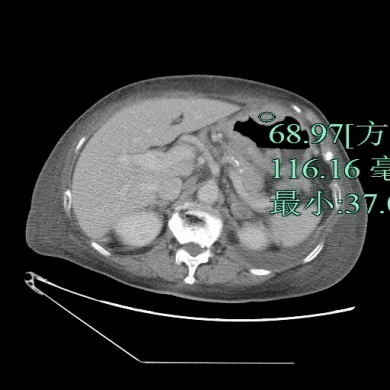

患者 , 女性 , 87岁 , 因咳嗽气急1周、发热4天入院 。 查体:未见明显异常 。 影像检查如下 , 以下哪个诊断最有可能?

文章图片

A.胃癌

B.肥厚性胃炎

C.淋巴瘤

D.神经内分泌肿瘤

E.间质瘤